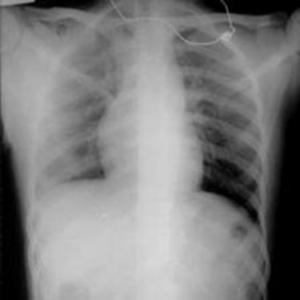

Ushbu platforma ko‘krak qafasi rentgen tasvirlarini sun’iy intellekt yordamida tahlil qilishga mo‘ljallangan bo‘lib, COVID-19, o‘pka fibrozlari, pnevmoniya hamda sog‘lom o‘pka to‘qimalarini to‘rt sinf bo‘yicha aniqlash uchun maxsus o‘qitilgan konvolyutsion neyron tarmoq (CNN) modelidan foydalanadi. Tizim tasvirni oldindan qayta ishlash, shovqindan tozalash va kontrastni kuchaytirish kabi raqamli algoritmlar asosida yuqori aniqlikdagi diagnostik xulosani taqdim etadi.